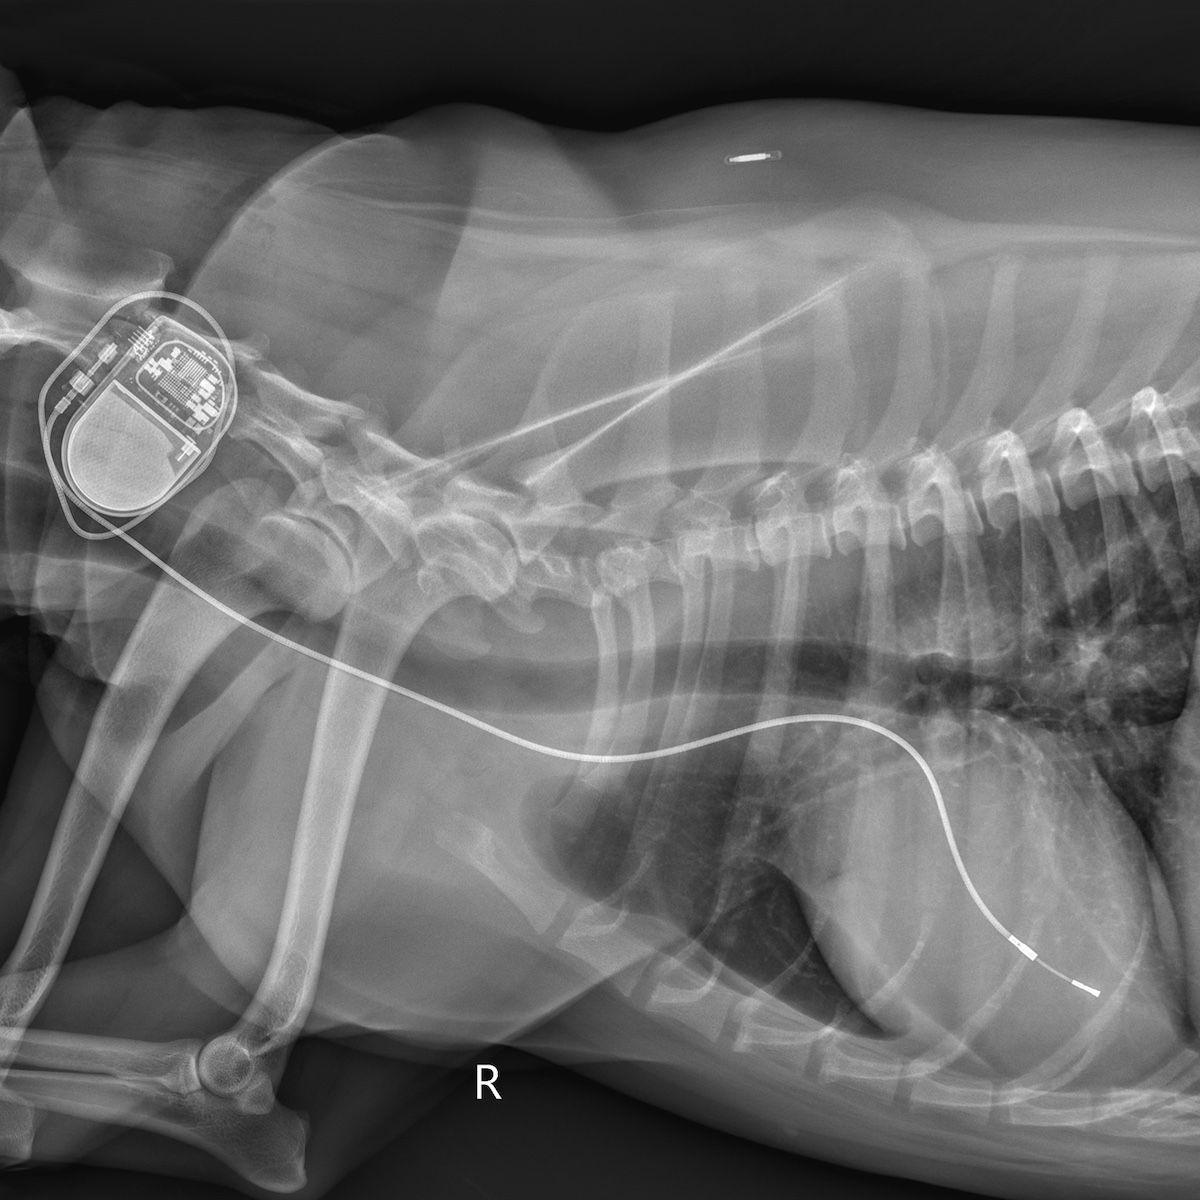

“The pacemaker is a life saver for animals like [this],” Samantha Eisner, DVM, a second-year cardiology resident in the SATH, who led the life-saving effort, said in a university release.1 “The reason the top and bottom chambers of her heart are losing the ability to communicate is because she has a damaged node, which means that it can’t press along the electrical signals that cause the heart to beat. The pacemaker bypasses the damaged node and stimulates contractions from inside the heart.”

Dogs with third-degree AV block will have heart rates between 20-40 bpm.2 An electrocardiogram (EKG) is required to confirm a diagnosis of third-degree AV block.2 The EKG will evaluate electrical activity of the heart and confirm whether there’s a lack of electrical conduction from the atria to the ventricles. It is then recommended to conduct an atropine response test, which involves a subcutaneous atropine injection.2

Ahead of a planned trip abroad, Sissy underwent a routine checkup for her health certificate, which is required to fly overseas. During the evaluation, the veterinarian noticed that her heart rate was significantly lower than it should’ve been. Despite the veterinarian’s initial doubt that the heart rate was an indication of further complications, he conducted an EKG as a precaution and ended up diagnosing Sissy with a third-degree AV block. Harrod acted quickly, researching next steps, and quickly determined that Texas A&M had the best veterinary cardiology program. After a quick email and phone call, Harrod and Sissy set off for help, and arrived at SATH 17 hours after she was diagnosed.